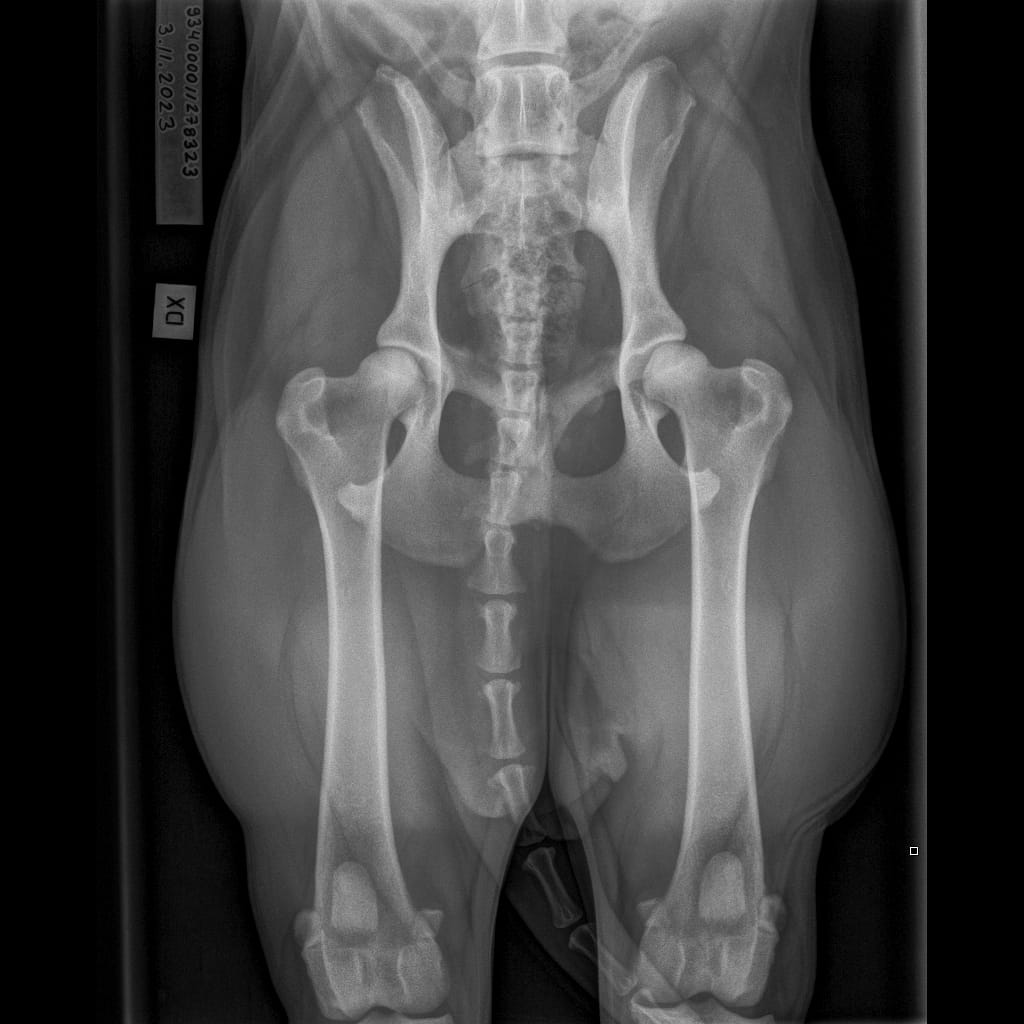

| Lumottu Uljas Iivonpoika ft. Finnridge | Sininen ♂︎ | 505 g | Ok | TBA | TBA | TBA | B/B | 0/0 | Ei todettu/Ei todettu | LTV1, SP0, VA1 | MH, laukausvarma | Low-grade MCT poistettu 06/2024 |

| Lumottu Aatos Iivonpoika ft. Finnridge | Turkoosi ♂︎ | 530 g | Ok | TBA | TBA | TBA | B/B | 0/0 | Ei todettu/Ei todettu | LTV2, SP0, VA0 | MH, laukausvarma | |

| Lumottu Martta Iivontytär ft. Finnridge | Lime ♀︎ | 525 g | Ok | TBA | TBA | TBA | A/A | Röntgen: 0/0 CT: 3/1 | Ei todettu/tulkinnanvarainen | LTV0, SP0, VA0 | MH, laukauskokematon (3) | |

| Lumottu Armas Iivonpoika ft. Finnridge | Oranssi ♂︎ | 440 g | Ok | TBA | TBA | TBA | A/A | 0/0 | Ei todettu/Ei todettu | LTV0, SP0, VA0 | MH, laukauskokematon (3) | |

| Lumottu Aulis Iivonpoika ft. Finnridge | Aqua ♂︎ | 440 g | Ok | TBA | TBA | TBA | B/B | 1/1 | Ei todettu/Ei todettu | LTV1, SP0, VA0 | Ohjaaja keskeytti | |

| Lumottu Irma Iivontytär ft. Finnridge | Pinkki ♀︎ | 550 g | Ok | TBA | TBA | TBA | C/B (matalat lonkkamaljat) | 0/0 | Ei todettu/Ei todettu | LTV0, SP0, VA0 | Tulossa 2024! | |

| Lumottu Sirkka Iivontytär ft. Finnridge | Pannaton ♀︎ | 390 g | Ridgetön | TBA | TBA | TBA | A/A | 0/0 | Ei todettu/Ei todettu | LTV1, SP0, VA0 |